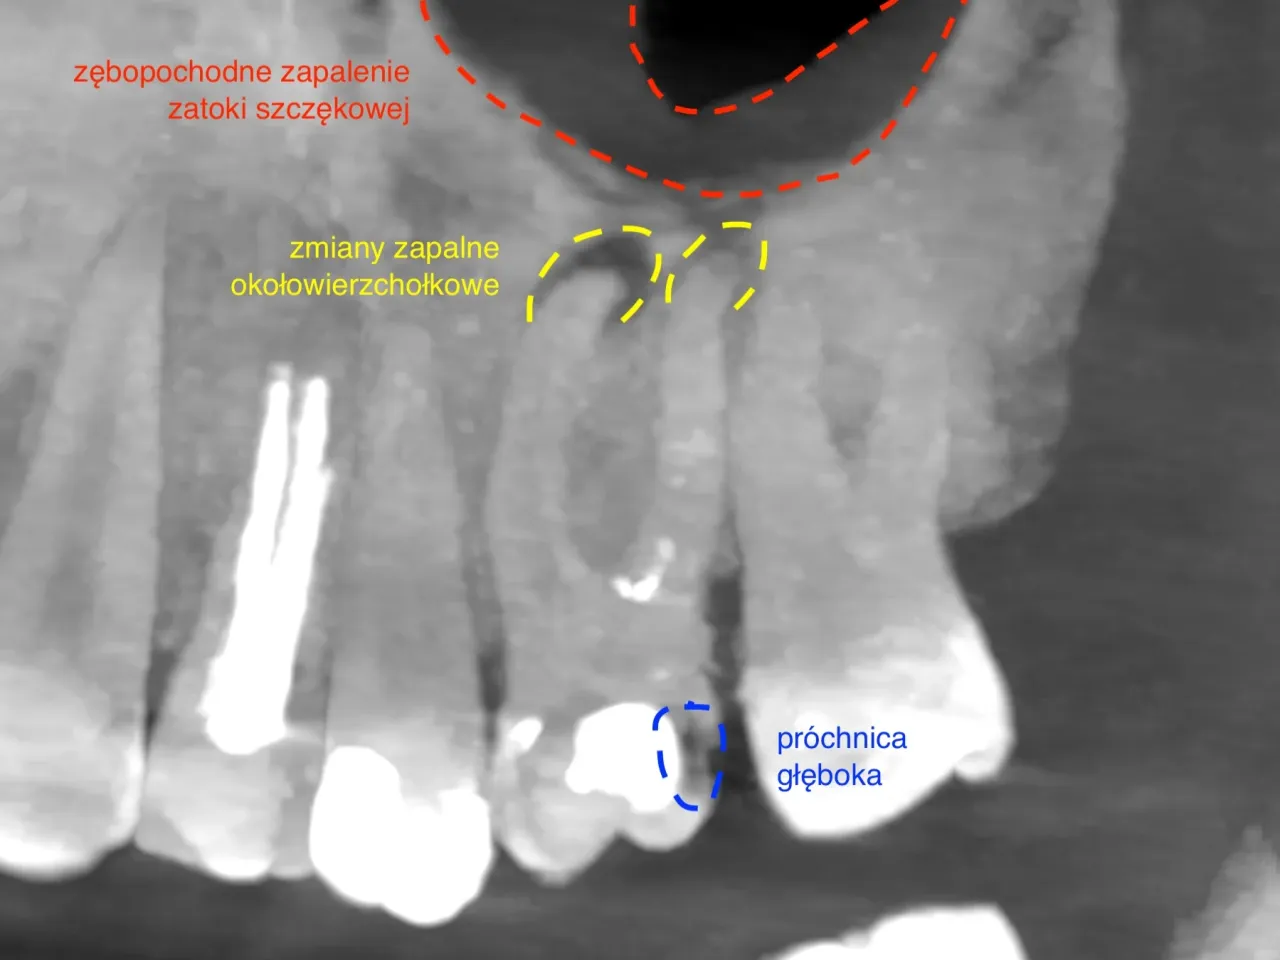

Podstawowym i absolutnie kluczowym narzędziem diagnostycznym, bez którego nie wyobrażam sobie rozpoczęcia leczenia kanałowego, jest zdjęcie rentgenowskie (RTG). Pozwala ono zobaczyć liczbę korzeni, ogólny zarys kanałów korzeniowych oraz ewentualne zmiany okołowierzchołkowe, czyli stany zapalne wokół wierzchołka korzenia. Choć RTG jest obrazem dwuwymiarowym i nie zawsze pokazuje pełen obraz trójwymiarowej anatomii, daje mi niezbędne informacje do zaplanowania wstępnego etapu leczenia i oceny, czy ząb nie ma jakichś oczywistych, nietypowych cech.

W przypadkach szczególnie skomplikowanych, kiedy standardowe RTG nie daje mi pełnej pewności co do anatomii zęba, lub gdy podejrzewam bardzo nietypowe rozwiązania, sięgam po tomografię komputerową wiązki stożkowej (CBCT). To zaawansowana metoda diagnostyczna, która dostarcza trójwymiarowego obrazu zęba i otaczających tkanek. CBCT pozwala na bardzo dokładną analizę anatomii korzeni i kanałów, w tym wykrycie kanałów niewidocznych na standardowym RTG, a także ocenę ich przebiegu, zakrzywień i ewentualnych rozgałęzień. To bezcenne narzędzie w trudnych sytuacjach.